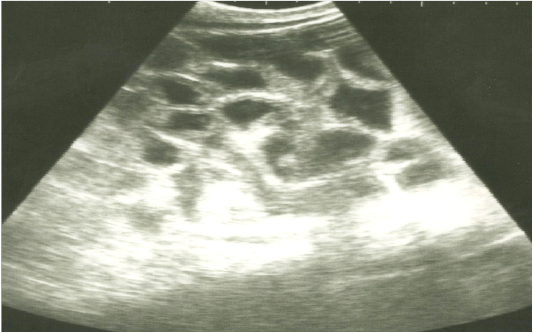

Ultrasonographic image of the left abdomen of horses with colic associated with enteritis and/or colitisusing 3.5 MHz transducer. The intestinal loops appear distended with fluid contents; the intestinal wall is slightly thickenedand corrugated. Increased intestinal motility of the intestinal loops was detected on the screen.